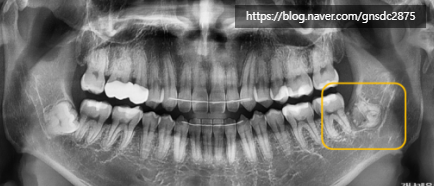

타치과에서 사랑니 발치를 하다 신경관이 가까워

뿌리를 남긴 채로 마무리하신 분입니다.

표시한 곳에 뿌리가

신경관가 가깝게 위치하여 남아있는 것이 보입니다.

발치 한달 후 발치부위의 불편감이 들어

남은 뿌리의 발치를 원해

강남레옹치과에 방문해주셨습니다.